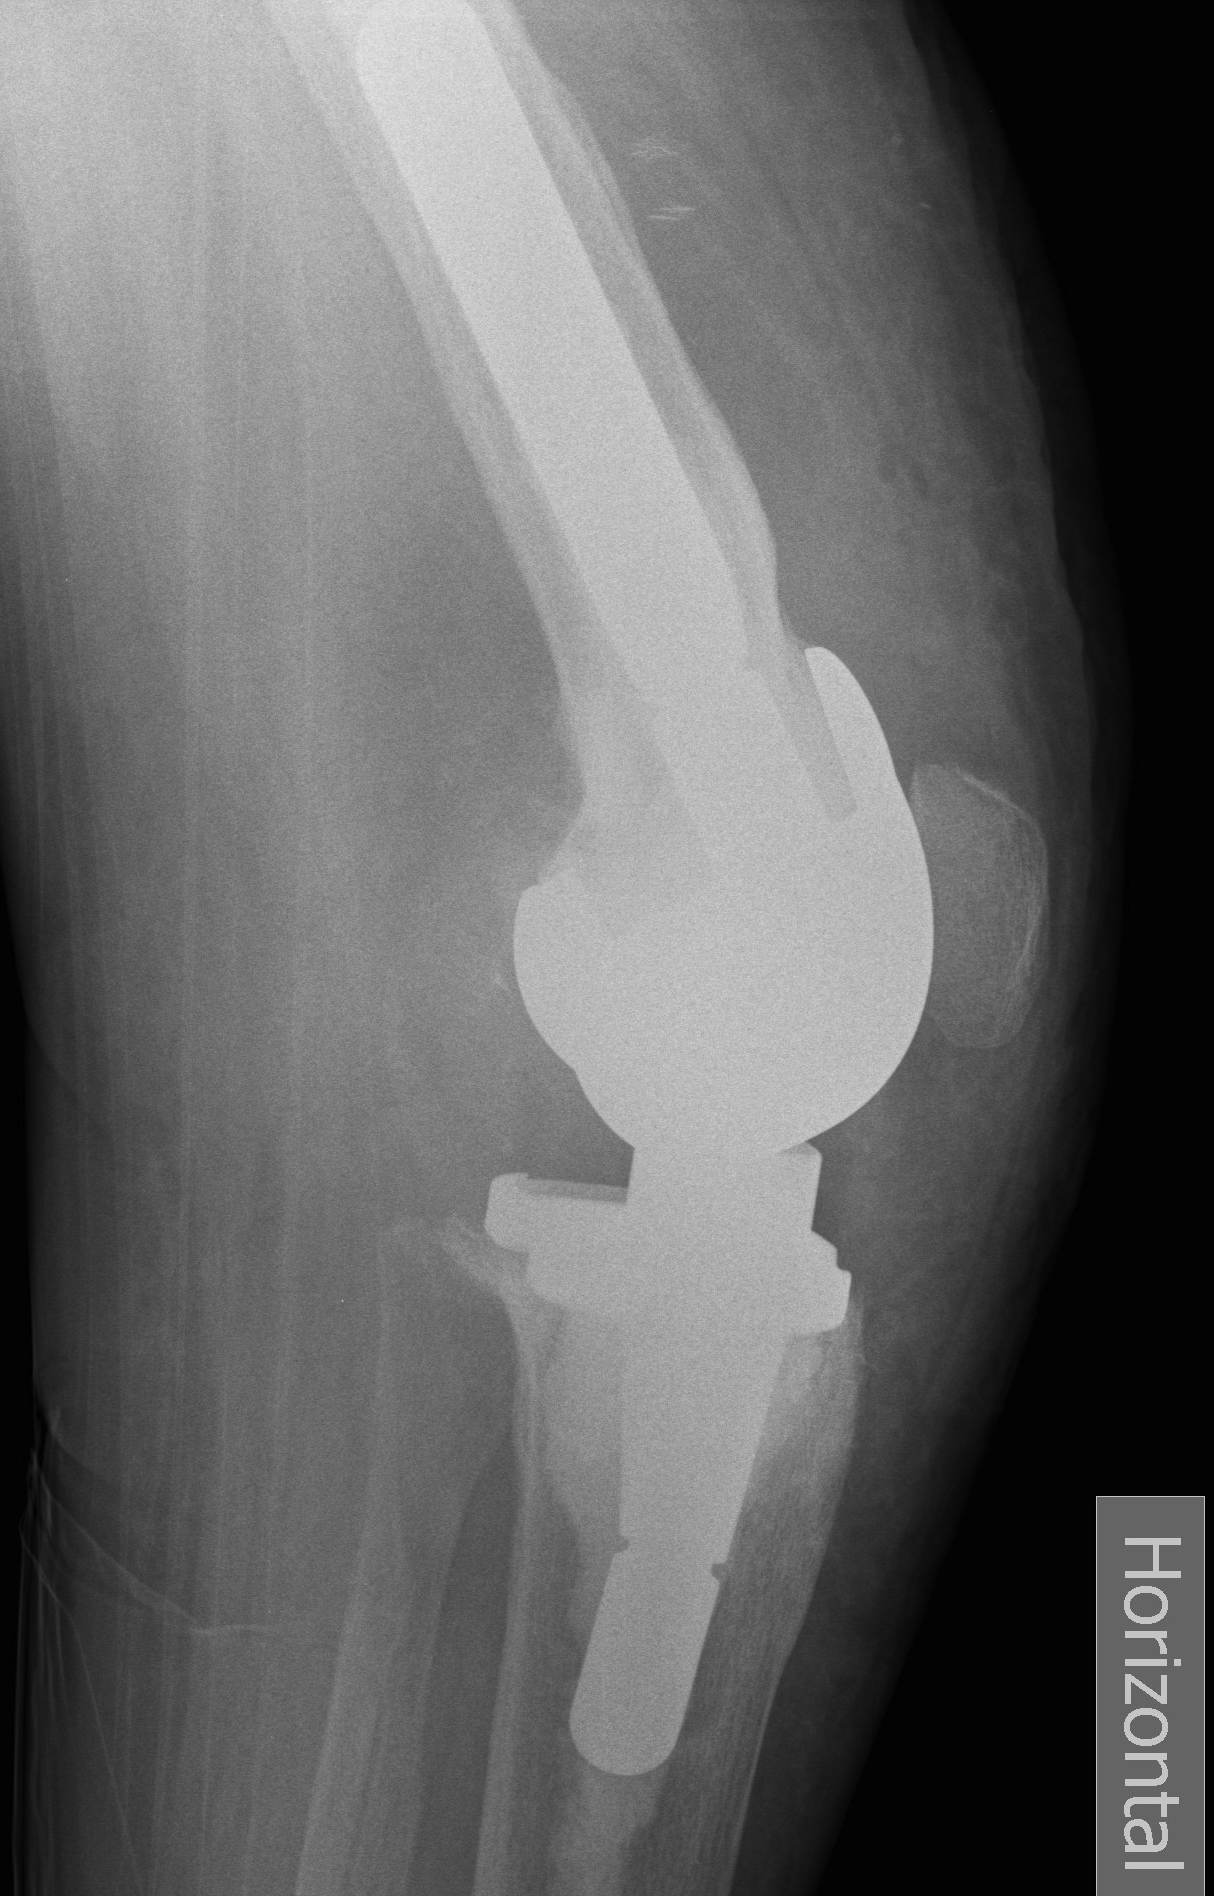

PC substituting / PS

Design

1. Tibial PE post with a femoral cam

- femoral cam engages the post at a designed flexion point

- prevents femur translating anteriorly

- with further flexion get rollback

2. Deeply dished articular surfaces

- increased conformity

3. "Third condyle"

- limits excessive tibial translation